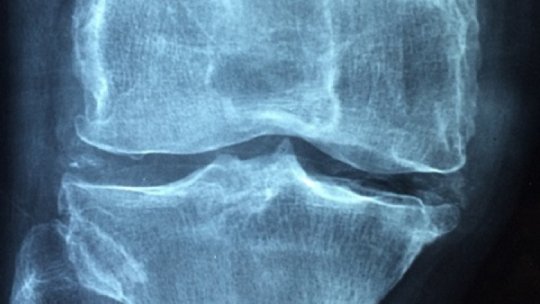

Osteoartrita este uzura articulațiilor. Este foarte frecvent, chiar omniprezent odată cu vârsta, deoarece de la 75 de ani, 70...